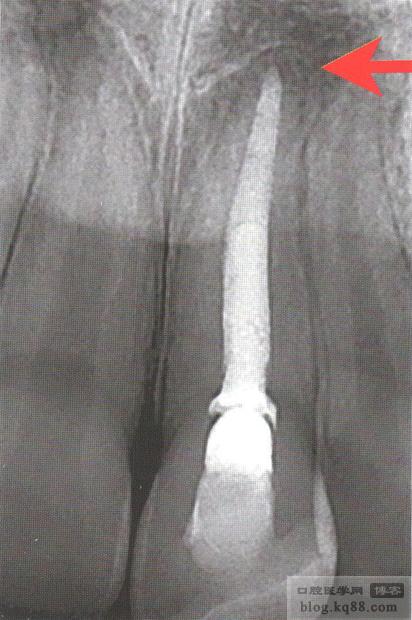

6、第二天復(fù)診,檢查MTA已完全凝固且封閉良好后,根管上段用牙膠封閉至秞牙骨質(zhì)下方 ,如做樁留出空間

7、復(fù)查X片(紅色箭頭處)顯示根尖封閉良好 ,達(dá)到又快又好的效果